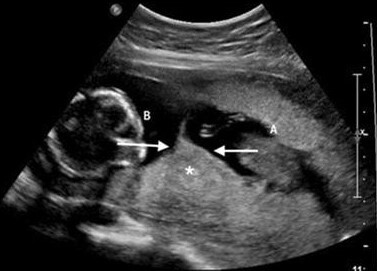

Q

Doppler ultrasound demonstrates twin A umbilical artery flow oriented towards twin B…

A

Think TRAP/twin reversed arterial perfusion syndrome (Twin A is the pump twin acting as the functional heart for the acardiac twin B)